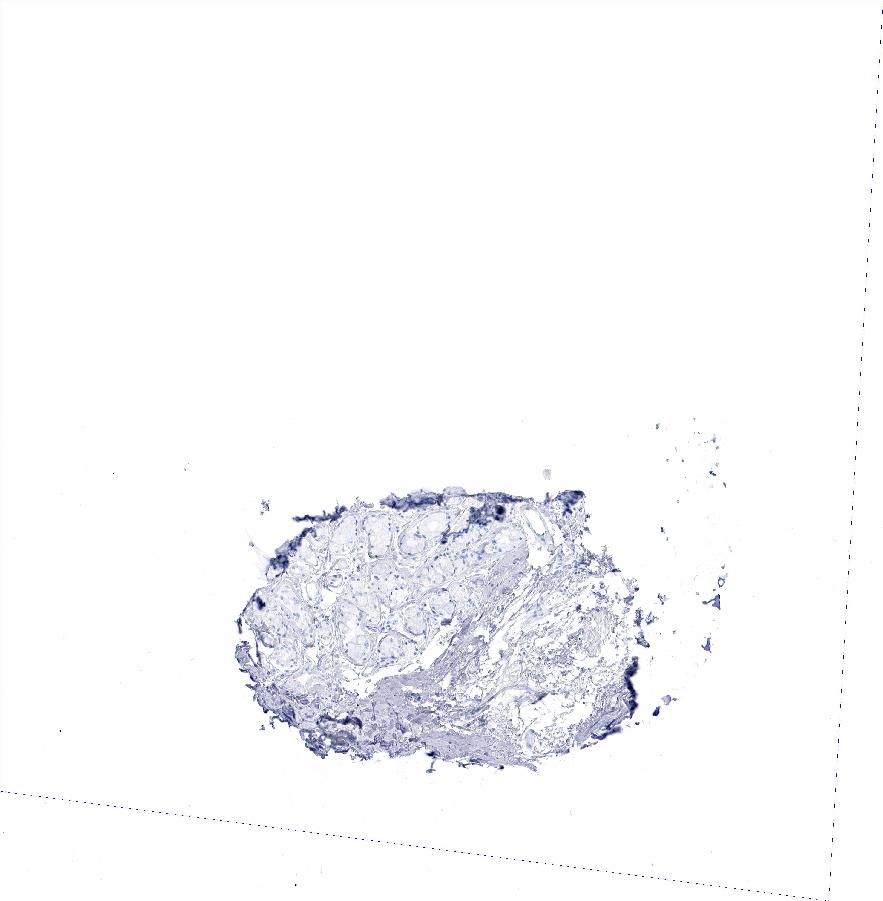

ADIPOSE TISSUE - Antibody stainingi

Antibody staining in the annotated cell types in the current human tissue is reported as not detected, low, medium, or high, based on conventional immunohistochemistry profiling in selected tissues. This score is based on the combination of the staining intensity and fraction of stained cells.

Each image is clickable and will lead to virtual microscopy that enables deeper exploration of all samples and also displays staining intensity scores, fraction scores and subcellular localization as well as patient and tissue information for each sample.

Antibody HPA019141Antibody CAB000047

Adipocytes Not detectedNot detected